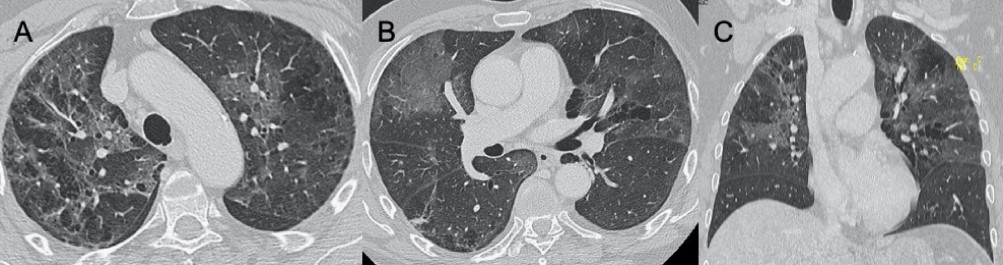

● CXR:肺胸膜下實(shí)變、磨玻璃影、結(jié)節(jié)和網(wǎng)狀結(jié)節(jié)陰影,表現(xiàn)為間質(zhì)性肺炎伴彌漫性肺泡損傷(圖1)。

● CT:早期主要為外周、雙側(cè)磨玻璃影(ground-glass opacities,GGO),伴實(shí)變、小葉間隔和小葉內(nèi)間隔增厚,形成“鋪路石征”模式。空氣支氣管征、血管擴(kuò)大、暈輪征和反暈征也有報(bào)告(圖2)。

圖1 新冠肺炎(COVID-19)的CXR。3例仰臥位CXR顯示胸膜下實(shí)變(箭頭),圖(A,B)顯示雙側(cè)受累,(C)主要為右肺受累

圖2 COVID-19的HRCT。急性期,雙肺(A)彌漫性GGO,小葉周圍型(B)。圖(C,D)顯示2例亞急性間質(zhì)性肺炎,GGO減少,存在胸膜下局灶性實(shí)變和小葉間/小葉內(nèi)間質(zhì)增厚。